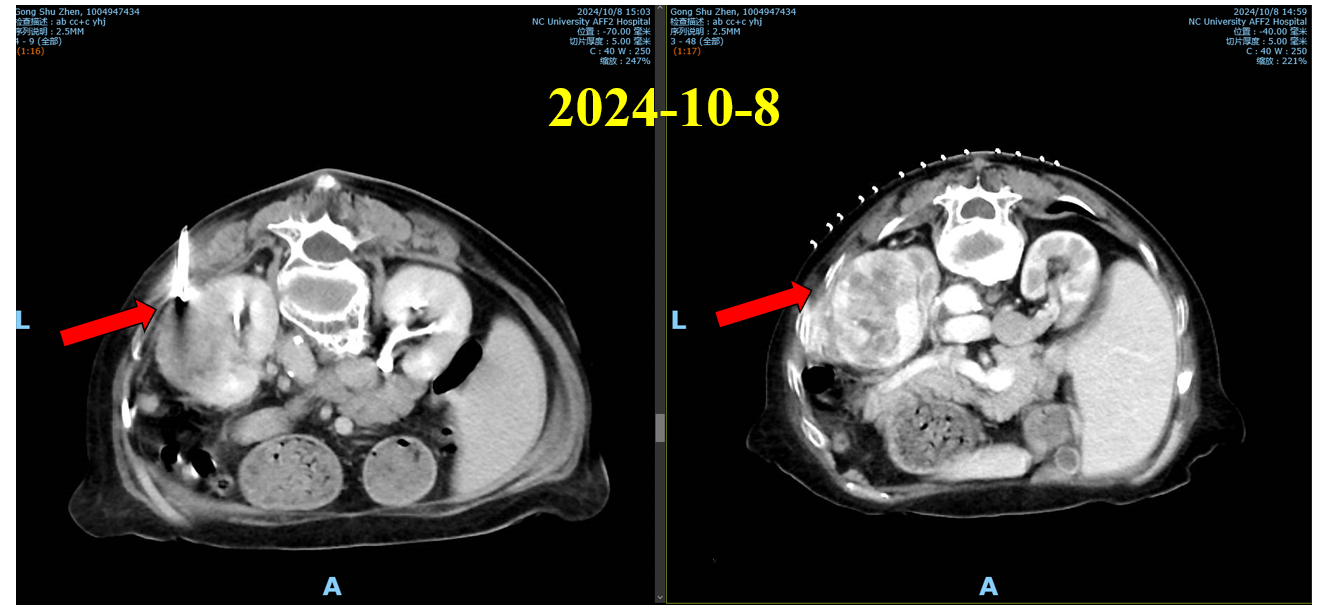

中腹部+盆腔CT增强CT:左肾占位,考虑恶性肿瘤,肾癌累及脾脏、不排外左腹壁侵犯可能,建议结合临床及组织学检查。

肾癌T4N0M1 IV期。 IMDC:3分,高危。

2024-10-9开始行培唑帕尼片 3片(600mg) qd po(患者拒绝行TKI+PD-1抑制剂)。